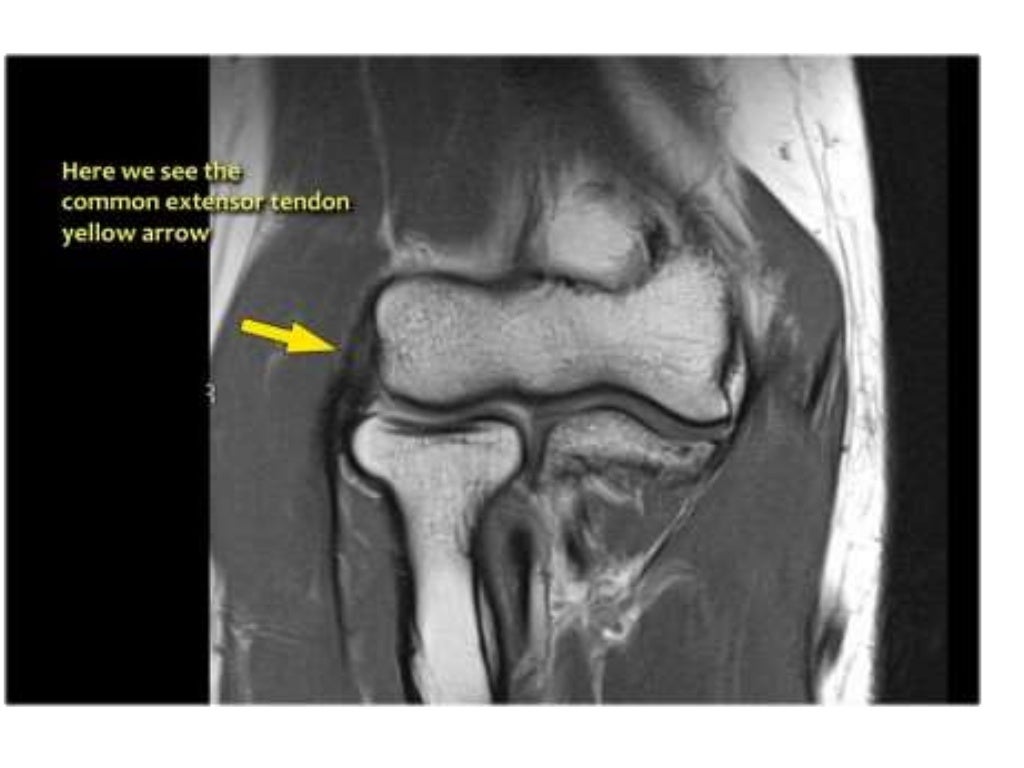

From www.imaginginnovated.co.uk

Imaging Innovated Radiology Courses, Musculoskeletal MRI / Ultrasound Anatomy Mri Msk Explore detailed mri anatomy of the ankle with educational resources available on freitasrad.net. Musculoskeletal mri atlas wait a few seconds for all the images to load and scroll using your mouse wheel About anatomy mri magnetic resonance imaging is particularly well suited for the medical evaluation of the musculoskeletal (msk). Stanford msk mri atlas has served ~1.7m pageviews to users. Anatomy Mri Msk.